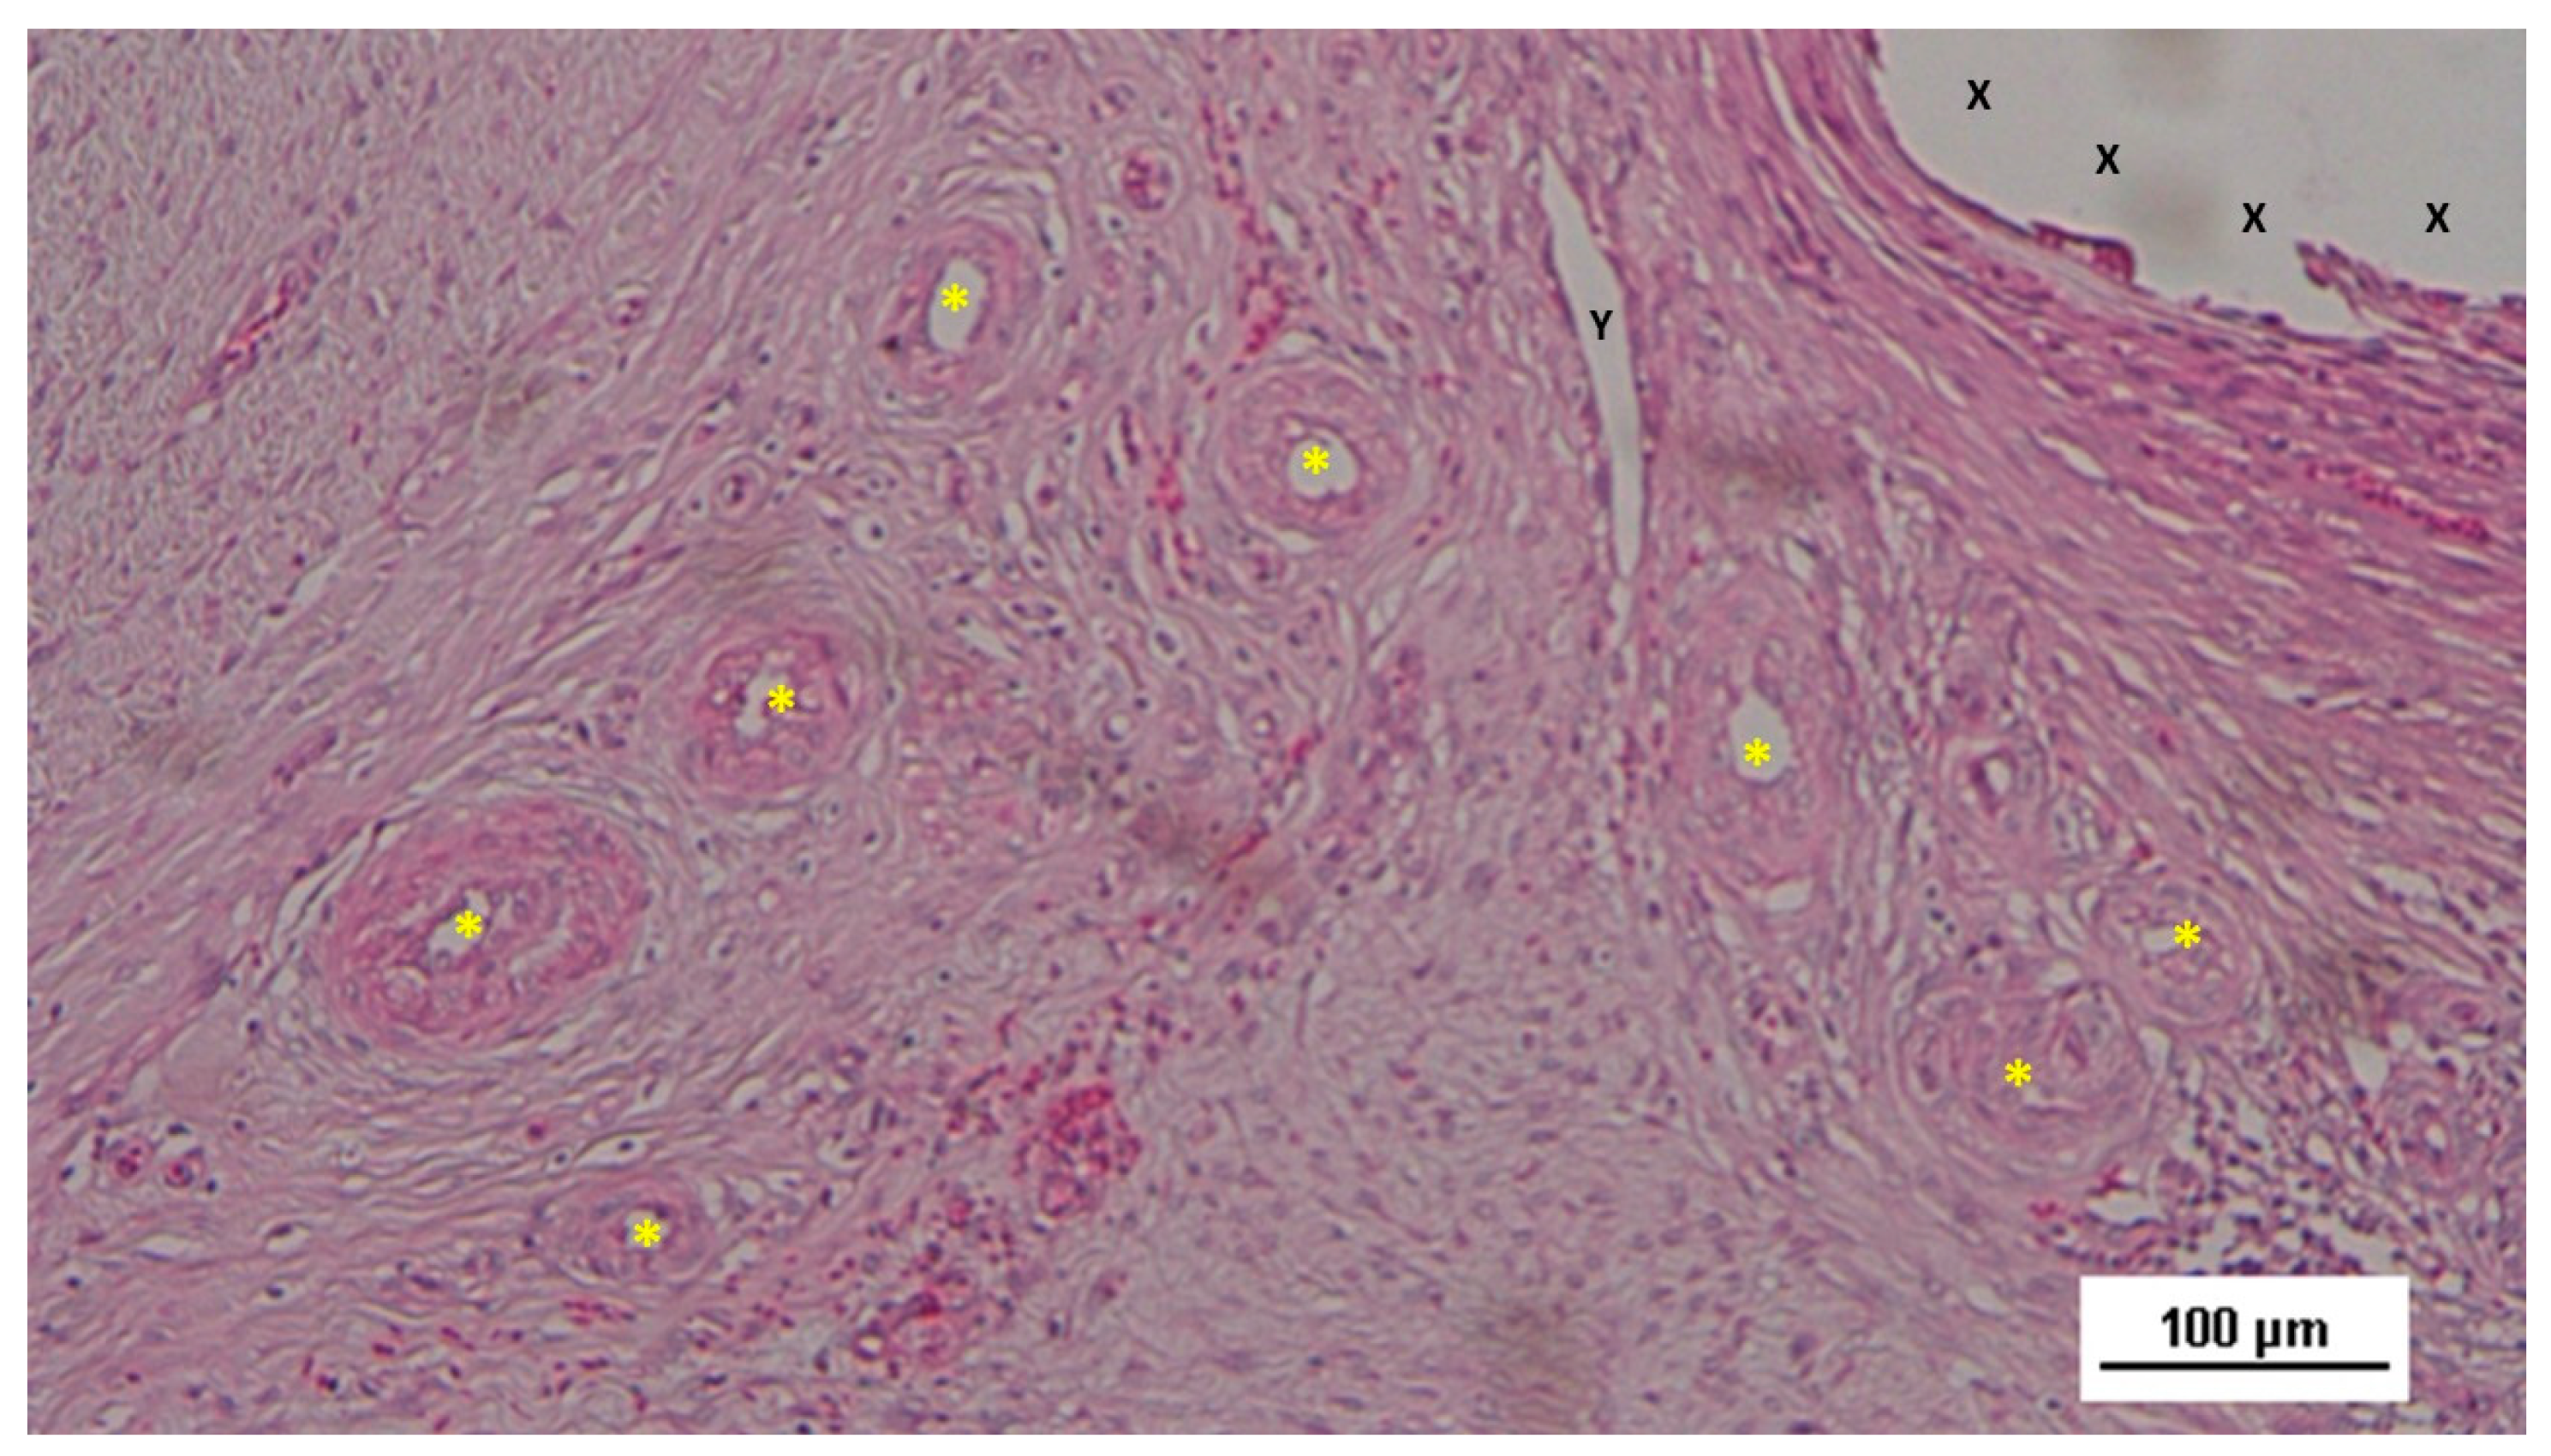

In the mid-term period (3-4 months post-implantation), H&E staining showed a significant presence of vascular structures within the S&S device. Notably, in this postoperative period no signs of inflammatory response against the fabric of the S&S device could be evidenced. The arterial structures displayed advanced development, with well-defined endothelial and muscular layers, while the adventitia was properly enveloping the vessels. Similarly, the veins exhibited noticeable structural maturation compared to the earlier period (Figure 7, Figure 8 & Figure 9).

Figure 12. Biopsy specimen from the 3D scaffold of the S&S device, six months post-surgery. In a matrix of slack, well-perfused connective tissue, several fully developed arterial structures (*) with thickened media are visible. A mature vein (Y) is located near the 3D scaffold fabric (X), which is free from inflammatory infiltration. HE 100X.